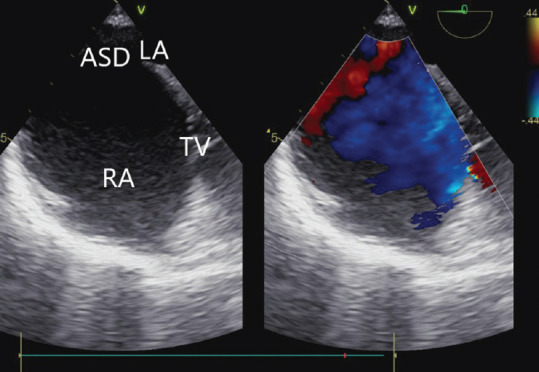

全肺静脉连接异常(TAPVC)是一种罕见的紫绀型先天性心脏病,成年后存活的患者更是少之又少。在此,我们介绍了一例 26 岁女性的病例,她在怀孕期间偶然被诊断出患有心上型 TAPVC。所有四条肺静脉汇合成一条共同的静脉汇流口,排入一条左侧垂直静脉,该静脉排入腹股沟静脉。

Total anomalous pulmonary venous connection (TAPVC) is a rare cyanotic congenital heart disease and their survival into adulthood is even rarer. Here, we present the case of a 26-year-old female who was incidentally diagnosed with a case of supracardiac TAPVC during her pregnancy. All four pulmonary veins were joining to form a common venous confluence which drained into a left-sided vertical vein which drained into the innominate vein.